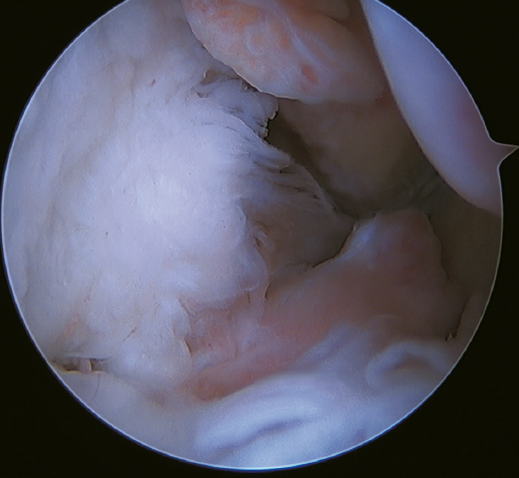

The main indication for this repair is rupture of the upper fascicle of the ATFL from its fibular insertion, with good tissue quality of the remaining ligament (Figure 3).

Figure 3. A: identification of the fibular insertion of the ATFL (*) with excellent quality of the tissue remnant; B: technique with two knotless implants and using a modified single anterolateral portal; C: final result. P: fibula; T1: talofibular tunnel; T2: calcaneofibular tunnel.